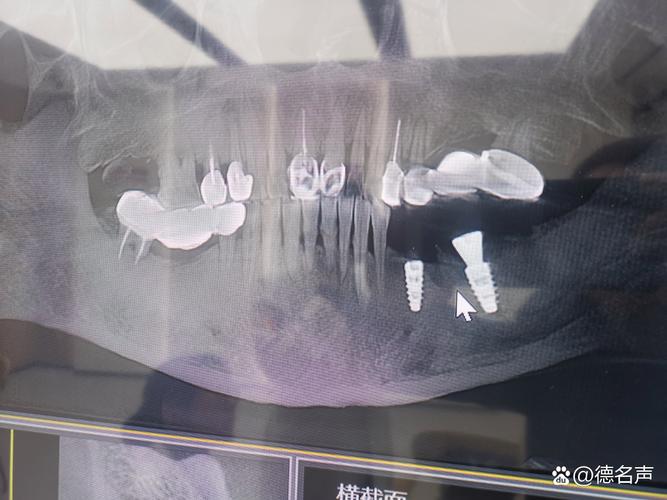

(图片来源网络,侵删)- 下颌神经管:需清晰显示其位置、走行及与牙槽嵴顶的距离(理想种植体植入点应距离神经管≥2mm)。

- 上颌窦:明确上颌窦底位置、黏膜厚度(正常1-2mm)、有无炎症或积液,避免种植体穿入上颌窦(需预留1-2mm骨壁)。

- 邻牙及牙周组织:观察邻牙牙根是否贴近牙槽嵴、有无根尖周病变、牙周袋深度,避免种植体损伤邻牙牙根或侵犯牙周间隙。

- 金属伪影:患者口内金属修复体(如烤瓷冠、金属桩)会产生伪影,需提前拆除或选择金属伪影校正(MAR)算法重建。